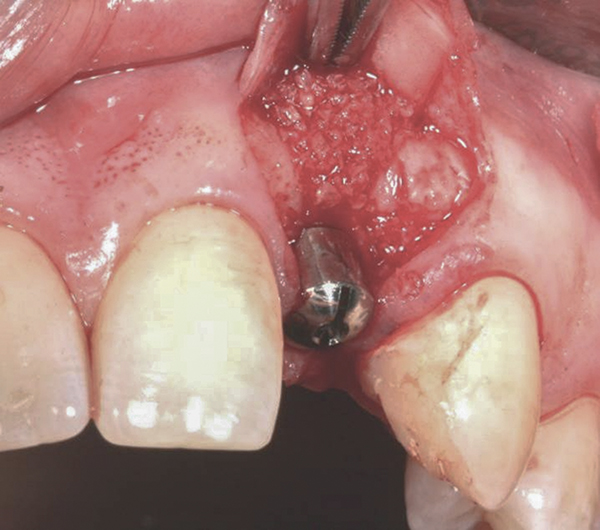

Fig 4. Implant inserted into the ridge, buccal view. There was a large labial concavity. The implant is seen on the buccal and terminates within the alveolar bone.

Figure 4

In the esthetic zone it is preferable to avoid elevating papillae because flap elevation may induce recession and create unesthetic black triangles.4 If a flap is necessary to perform a procedure in an edentate area when adjacent teeth are present, the following technique can be used to circumvent blunting papillae. Make a horizontal incision along the midcrestal or palatal aspect of the ridge and terminate the incision 1 mm from the adjacent teeth (Figure 1). The incision is created palatally if it is desired to transpose keratinized tissue to the buccal. From the horizontal incision, create bilateral buccal vertical releasing incisions that extend obliquely at an angle (Figure 2). The vertical incisions can also be extended palatally (for access), but this is not always necessary (Figure 3). Preserved papillae contain gingival supracrestal fibers that subsequently help maintain papillary height (Figure 4). The distance the incision is extended vertically on the buccal is dictated by the task to be accomplished (eg, implant insertion only requires short vertical incisions, while bone grafting needs longer incisions) (Figure 5 and Figure 6). At the end of the surgical procedure, the severed papillary segments are sutured to their retained counterparts (Figure 7 and Figure 8). Figure 1 through Figure 8 demonstrate a submerged implant protocol.

In Figure 1 through Figure 8, tooth No. 8 is missing. If abundant bone and keratinized tissue is present, a punch procedure (flapless) can be used to access bone to place an implant. However, a flap should be elevated if there is a lack of keratinized tissue or if bone grafting or soft-tissue repair is required. There are two available options with respect to raising a flap: elevate it and include the papillae, or use papillae-sparing incisions. Each procedure provides advantages and disadvantages.